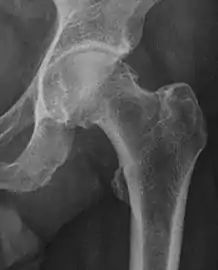

X-ray

Projectional radiography ("X-ray")is often considered first line for FAI.[10] Anterior-posterior pelvis and a lateral image of the hip in question should be attained.[10] A 45-degree Dunn view is also recommended.[10][19]

| Femoral head-neck offset | ![]() |

Offset of the femoral head with regard to most prominent aspect of the femora neck | >10 mm |

| Offset percentage | Femoral head-neck offset related to femoral head diameter | >0.18

| |